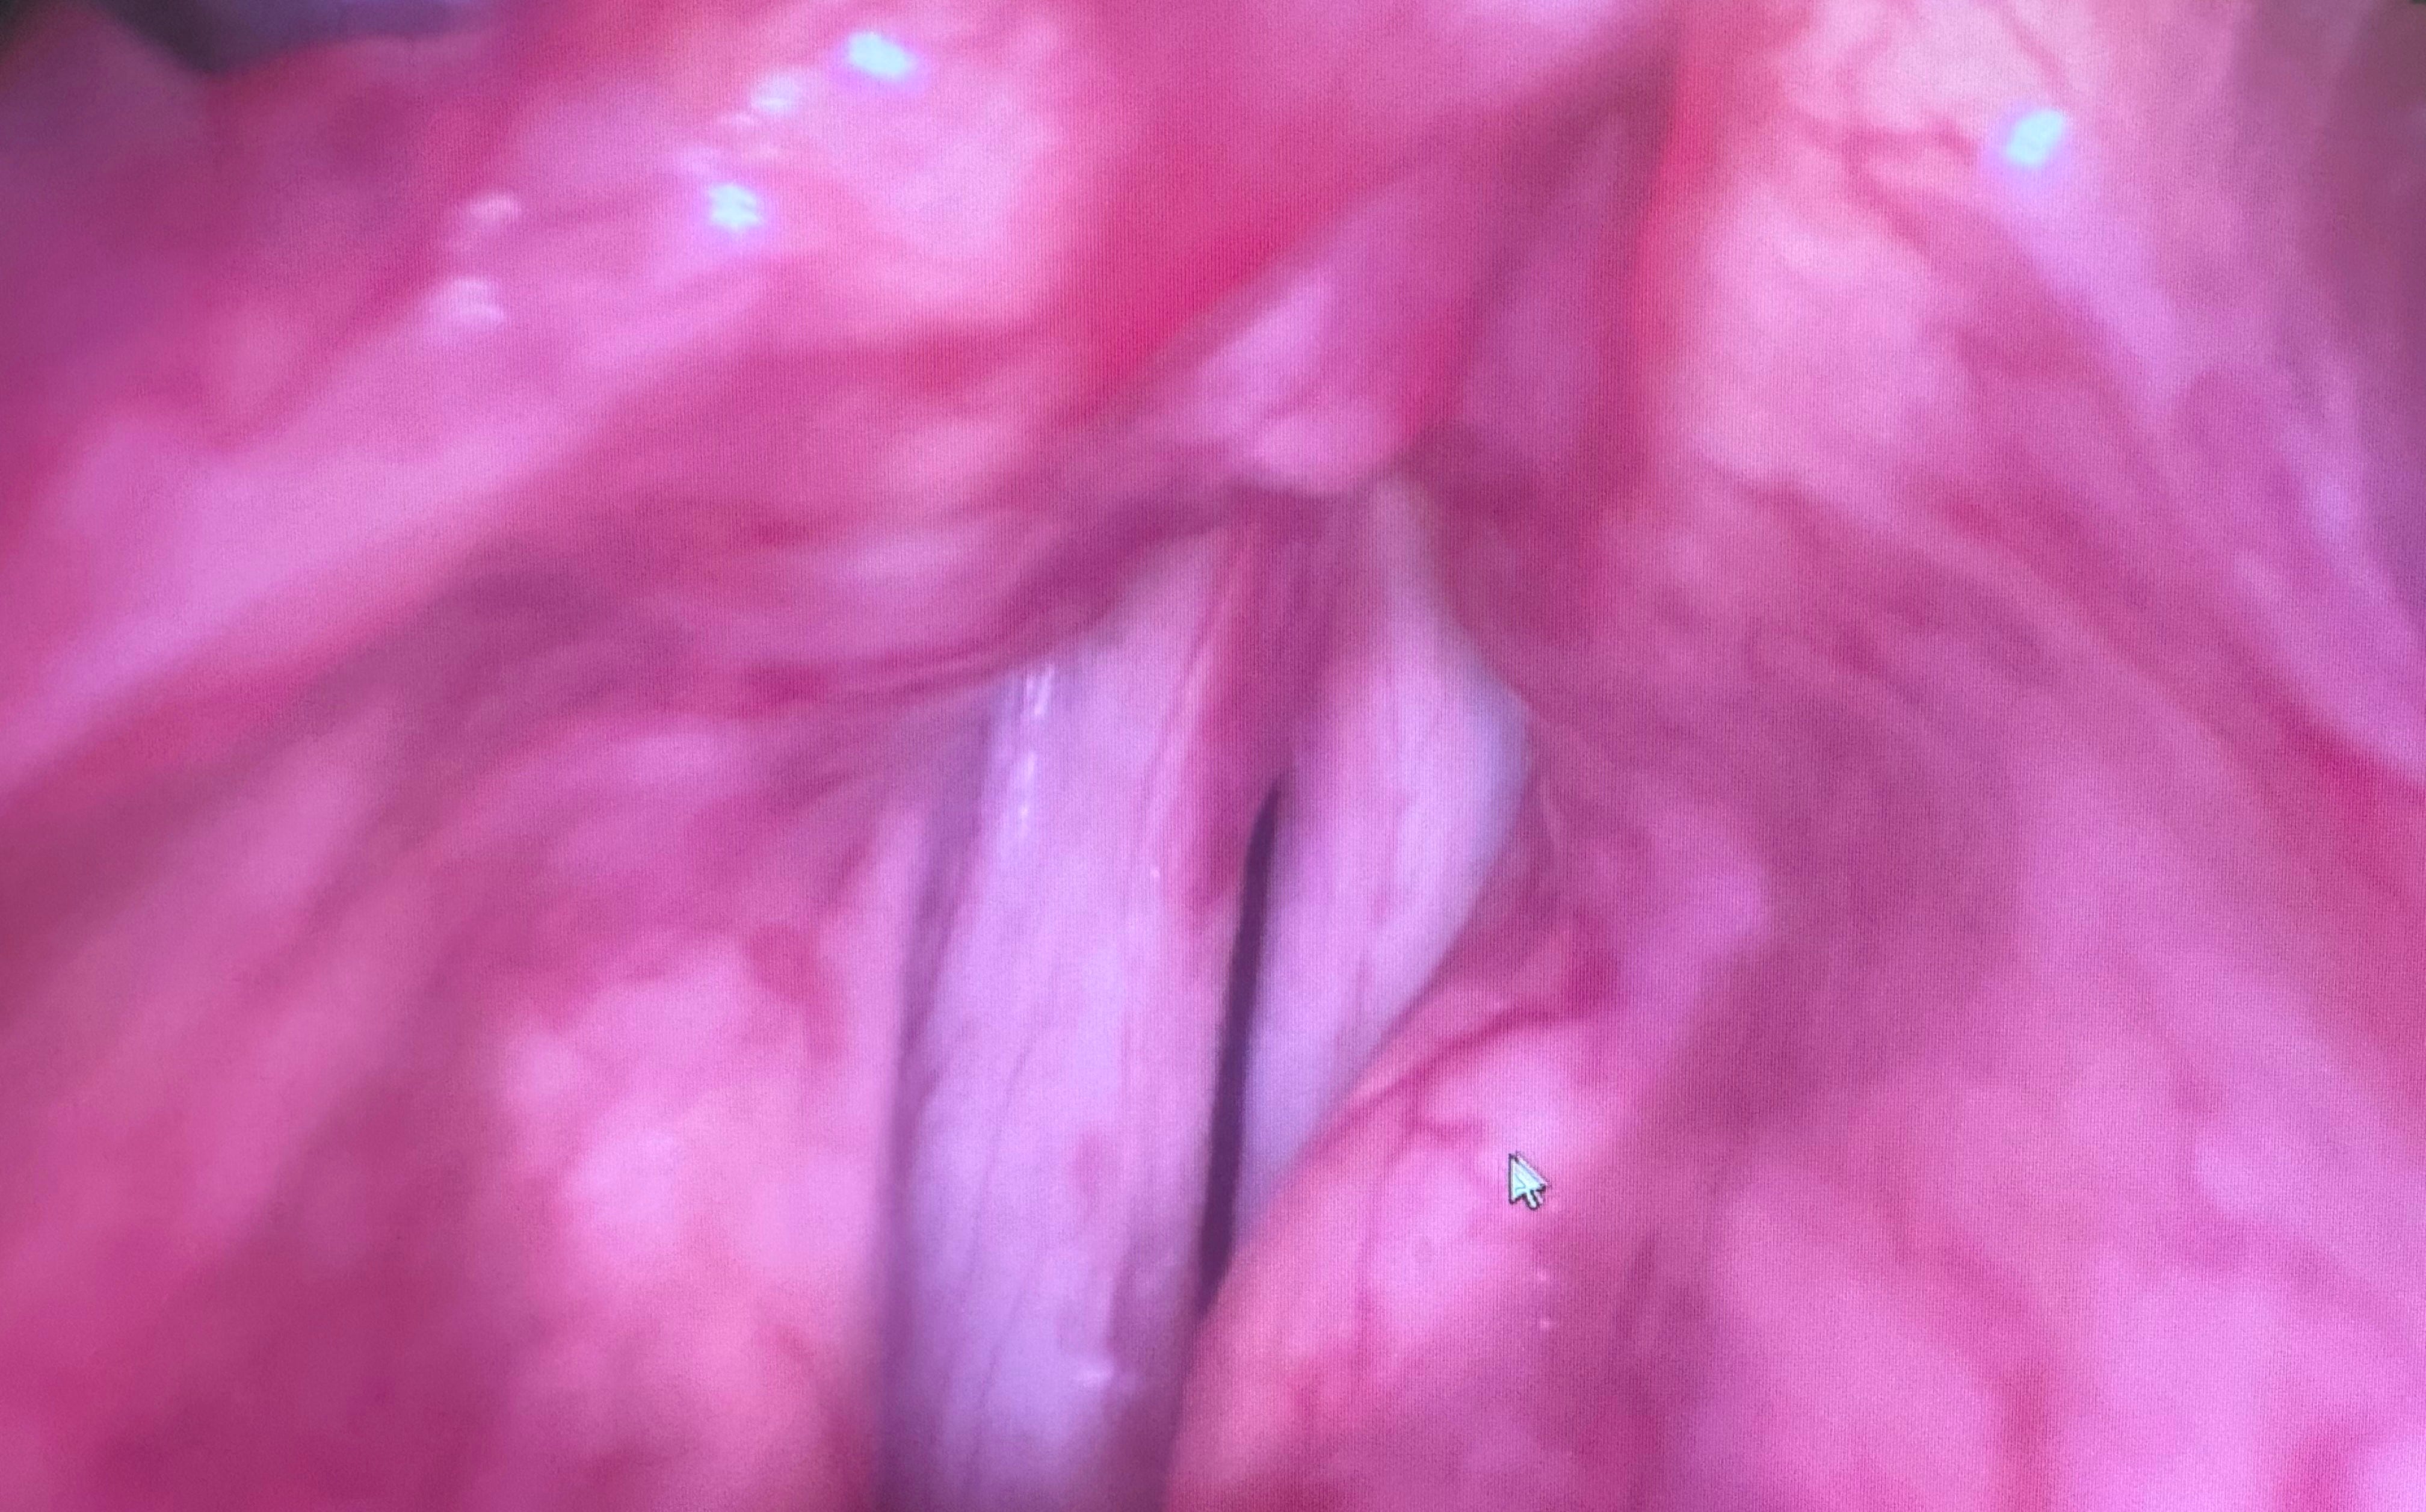

Recently viewed, stroboscopic image of my vocal cords triggered reflections on our personal power to transform ourselves. I know, it’s a leap, but please stay with me. I sought treatment for vocal cord irritation. Nothing serious is wrong. But I must take some voluntary actions to change. The striking, arguably disturbing, photograph above provides an i…